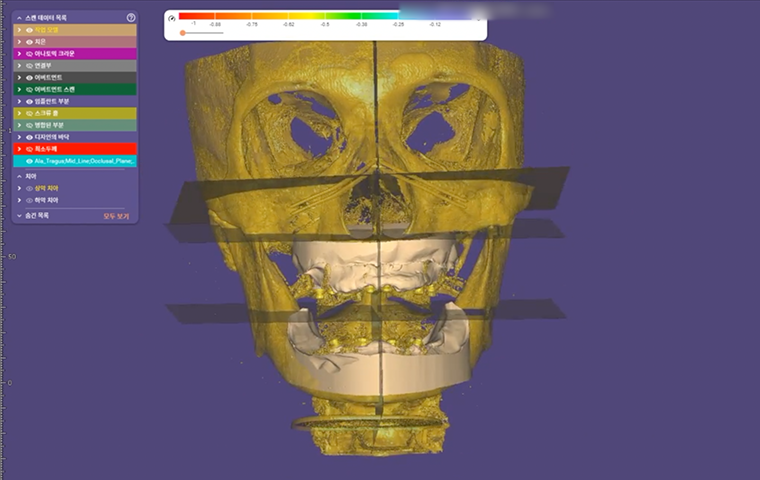

All-on-X

Practical Digital Prosthodontics: Understanding and applying

All-on-X treatment concept

Dr. Janghyun Paek

Professor at Kyunghee University, Department of Prosthodontics

All-on-X

Dr. Janghyun Paek

|

Practical Digital Prosthodontics: Understanding and Applying All-on-X Treatment Concept |

All-on-X

Dr. Janghyun Paek

|

Practical Digital Prosthodontics: Understanding and Applying All-on-X Treatment Concept |

Special Pre-Day Course

Practical Digital Minimalism

Dr. Janghyun Paek

Explore the digital implant dentistry, including the All-on-X treatment concept, guide surgery, immediate loading protocols, prosthodontic considerations, and soft tissue contouring. Course also includes hands-on for All-on-X implant placement, prosthodontic components, intraoral scan, and immediate loading.